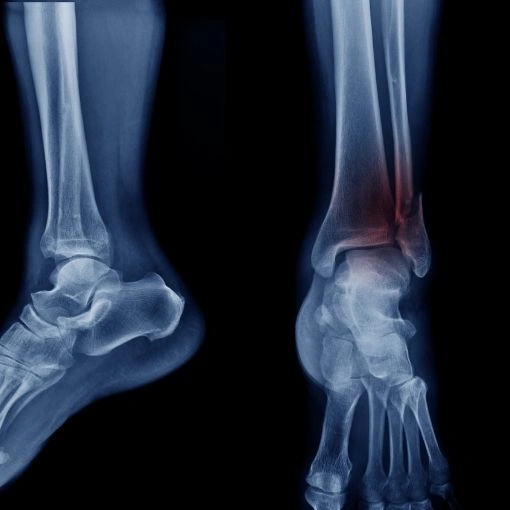

Ayak ve Ayak Bilek Cerrahisi

Ayak ve ayak bileği problemlerinin cerrahi tedavisi, halluks valgus, düz tabanlık ve diğer ayak deformiteleri.

Ayak ve Bacak Kırıkları

Ayak ve bacak kırıklarının cerrahi ve konservatif tedavisi, kırık iyileştirme süreçleri.